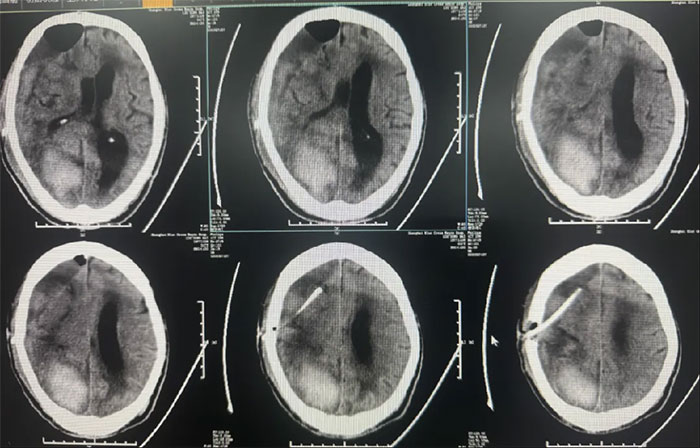

术后中线偏移明显改善,颅内压降低,停用脱水药物;

● 硬膜下血肿引流15天后拔管,中线基本复位,硬膜下血肿较前明显减少;